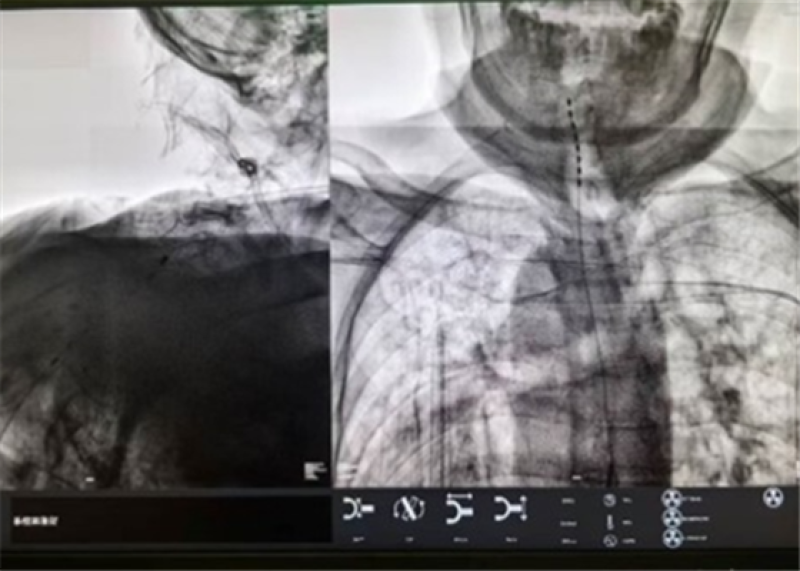

多例中青年人突发“换季卒中”,快速识别与急救是关键

防卒中、护大脑!湖南航天医院卒中中心实用指南来了